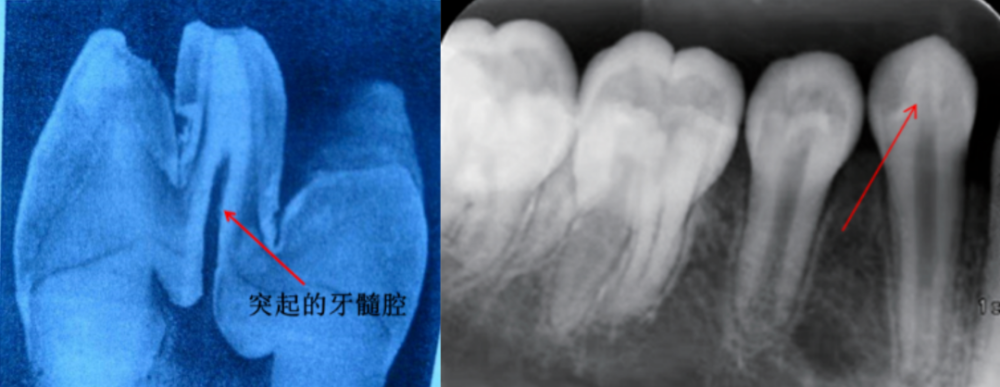

然后发现了这颗牙的问题,畸形中央尖,根尖喇叭口,慢性根尖周炎转诊我

由于畸形中央尖折断时多处于牙齿发育的阶段,如果引起牙髓或根尖周的

畸形中央尖中高耸的牙髓组织.part 03.有没有办法预防"中央尖"折断?

图2-22 乳磨牙的继承恒牙畸形中央尖折断值得注意的是,临床还可见到